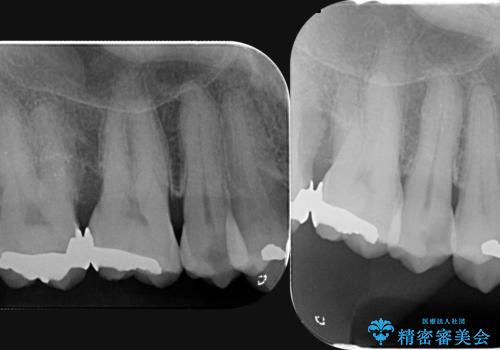

部分矯正を含む 歯周病治療 (再生治療・歯周ポケット除去・MTM・連結補綴)

検査の結果、強い歯ぎしりによる歯の周囲の骨の吸収が認められたため歯槽骨の再生・歯周ポケットの除去・力に対抗する連結補綴・補綴前処置としての小矯正を計画します。

特定の歯に強く力がかかりまた歯周病により臨床歯根が短くなっているような場合、歯の動揺を抑えるため連結補綴が検討されます。

歯の動揺が続くとより周囲の骨を失い最終的には歯を喪失してしまう可能性が高くなってしまうためです。

今回連結補綴を行うにあたり、歯周病の問題を解決するために再生療法・歯周ポケット除去手術を、またより歯の神経を保存し力に対抗できる環境を整えるために小矯正を行い精度の高いメタルボンドクラウンを製作することができました。